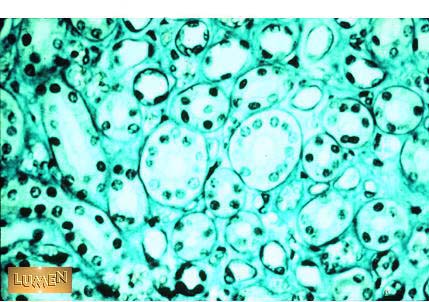

In this slide, what cells produce reticular fibers?

Fibroblasts (this is the kidney)